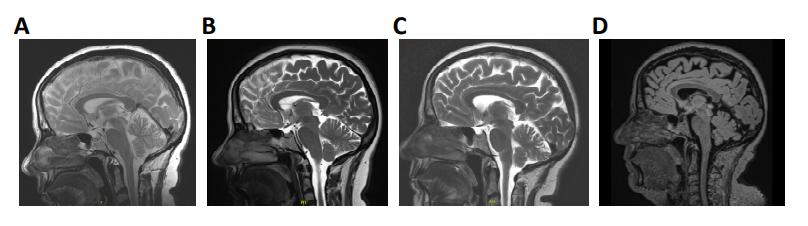

Supplementary Figure 1. Mid-sagittal T1/T2 and Flair-sequence MR images. Images were taken in

(A) 2010, (B) 2014, (C) 2019, and (D) 2024, respectively.